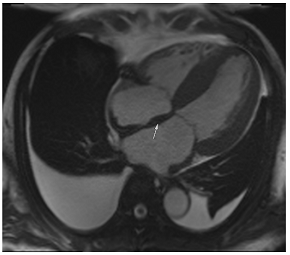

Figure 2.

Tissue characterization with Late Gadolinium Enhancement (LGE) and Extracellular Volume (ECV) Map. Adapted with permission from [33].

To avoid the low but important risks of endomyocardial biopsy, which can have an overall complication rate of up to 6% [2], myocardial fibrosis can be assessed non-invasively using CMR: LGE is suitable for detecting irreversible replacement fibrosis and myocardial scarring and T1/ECV mapping for detection of potentially reversible (reactive) interstitial and more diffuse fibrosis (not detectable by LGE) (Figure 2).

9. Tissue Characterisation with Late Gadolinium Enhancement

LGE has become the reference standard for non-invasive imaging of myocardial scar and focal fibrosis [40]. Gadolinium chelates are interstitial agents that cannot penetrate healthy intact cell membranes. Therefore, they remain in the interstitial space and accumulate in areas of cell injury/necrosis and focal fibrosis where this is expanded, while in healthy regions, contrast more readily washes out [41]. Specific LGE patterns are seen in different diseases (e.g., subendocardial fibrosis in CAD, patchy epicardial/mid-wall fibrosis in areas of hypertrophy in HCM). Minor areas of LGE can be detected in up to 50% of patients with HHD, but there is no specific pattern (in 95% of the non-ischaemic LGE distribution) [42]. If present, LGE is often found in the basal to mid-septal, inferior, and inferolateral segments in patients with HHD [42]. The severity of diastolic dysfunction increases with the extent of fibrosis by LGE [25,31]. Furthermore, focal fibrosis/LGE may be a substrate for ventricular arrhythmia and is associated with sudden cardiac death [31].

Myocytes account for approximately one-third of all cells in normal myocardium. The remaining two-thirds of cells include endothelial and vascular smooth muscle cells and fibroblasts in interstitial/perivascular spaces [2] (Figure 2). Normal CMR ECV values vary between 25.3 and 3.5% [43]. Ideally, age- and sex-corrected normal values for ECV should be used [44]. Hypertension affects both the cellular and extracellular compartments of the myocardium. In addition to cardiomyocyte hypertrophy, in HHD, fibrous tissue (primarily type I fibrillar collagen) is deposited in the extracellular matrix over time and leads to increased tissue stiffness (i.e., diastolic dysfunction) [2]. ECV values are higher in hypertensive patients with LVH than in patients without LVH, and eccentric forms of hypertrophy seem to have the most fibrosis and highest ECV values, together with more pronounced systolic impairment and are associated with a poor cardiovascular prognosis (Figure 1) [2,6]. CMR-derived T1 mapping and strain analysis seem to be related, but an adequate comparison of the performance of these parameters is often limited due to the lack of harmonization of measurement methods [35]. Furthermore, ECV values seem to correlate with many blood biomarkers associated with (i) systemic inflammation; (ii) metabolism; (iii) fibrosis; (iv) chemotaxis; and (v) platelet activation [6]. This may suggest that an increase in ECV in hypertensive patients is a (non-specific) imaging biomarker of inflammation, tissue remodelling, atherogenesis, or metabolic disorder in patients with HHD [6]. Given the clinical consequences of myocardial fibrosis in HHD and considering the potential for recovery of fibrosis with appropriate treatment, the need for an accurate diagnosis of myocardial fibrosis is apparent.